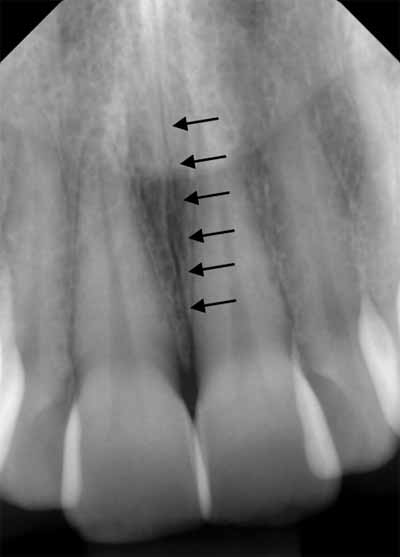

歯槽骨に、薄くわずかに湾曲したエックス線透過性の線が見えることがあります。これらは栄養管であり、神経と血管のための骨内の小さな空洞です (画像5を参照)。多くの場合、上顎洞の壁でもこれらの栄養経路を識別できます。